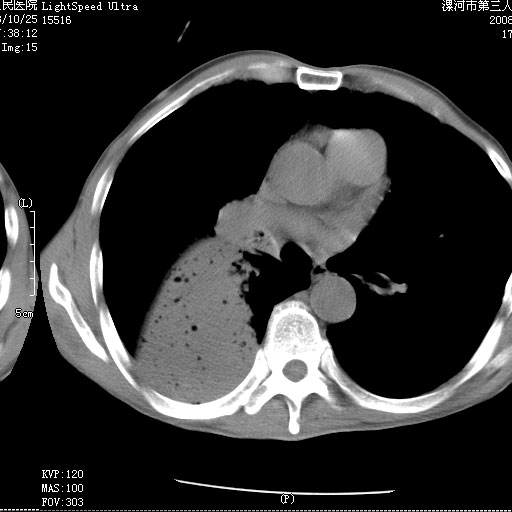

m 老年 发烧、呼吸困难,慢支、肺气肿多年;记的那次是下午大概17:38做的,晚上窒息死亡。

上面的层面就慢性支气管炎肺气肿、肺大泡,别的没有什么、也就不传了。

当时我怀疑:1、阻塞性肺不张早期 2、肺脓肿早期,望老师们发表意见

考虑为右肺下叶支气管痰栓形成并阻塞性肺不张及肺炎。

按肺叶分布,考虑肺不张

病变按肺叶分布,病变内可见多个小空腔影,未见充气支气管影,中间段支气管管腔肺窗示密度欠均匀,下肺支气管分叉处基底段支气管隐约可见,未见明显狭窄,中叶支气管通畅,

考虑:阻塞性肺炎伴小脓肿形成可能性大。(痰栓可能性大)

右下肺实变,内有弥漫分面小气泡而无支气管征,叶间裂前移,呈臌大之形,而无收缩之状,兼纵隔稍左行移,故。不支持不张,倒支持大叶肺叶,如楼上所说,小气泡不象残留之肺,不可以考虑产气菌感染吗。

阻塞性肺炎,肺脓肿形成。依据,右下支气管不通,大片实变形内可见小气泡。不支持肺不张。